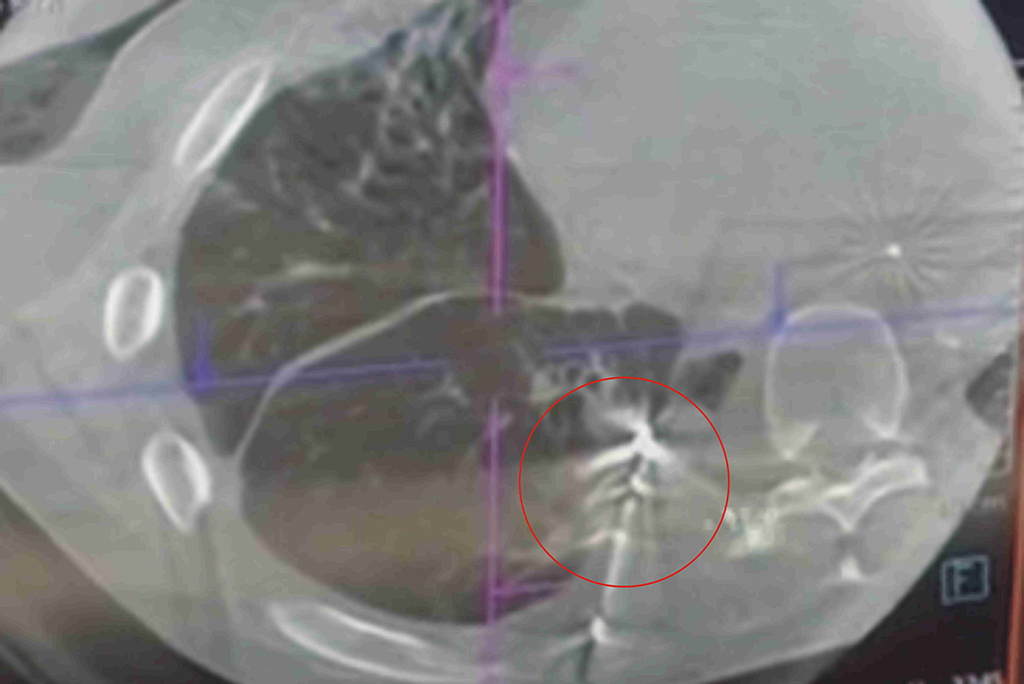

呂俊佑醫師指出,一位84歲男性被診斷為左側肺癌,腫瘤組織檢查顯示存在EGFR突變,經超過一年的第三代標靶藥物治療,患者的療效良好,且副作用控制在可接受範圍內。

84歲男性患者,被診斷為左側肺癌,腫瘤組織檢查顯示存在EGFR突變。

84歲男性患者,經過超過一年的第三代標靶藥物治療,療效良好。